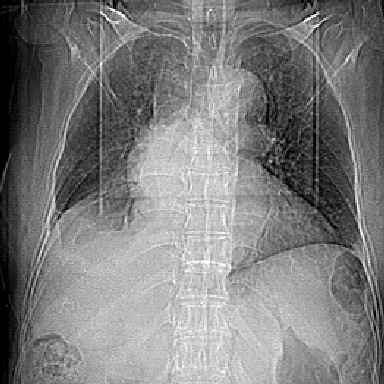

以下是引用swyyy2007在2007-4-13 15:31:00的发言:[br]右肺门下区肿块,右肺下叶支气管阻塞,右肺下叶不张,右侧大量胸腔积液,右肺中叶见结节状高密度影,边缘清,纵隔内见肿大淋巴结。首先考虑右下肺中心型肺癌伴右肺下叶不张、中叶、纵隔淋巴结转移。右侧胸腔积液。

以下是引用苯小孩在2007-4-13 16:20:00的发言:[br]1、右下肺中央型肺癌并阻塞性肺不张、肺内转移、胸椎右侧附件亦有转移<横断层面第8层>.[br]2、右侧胸腔积液.